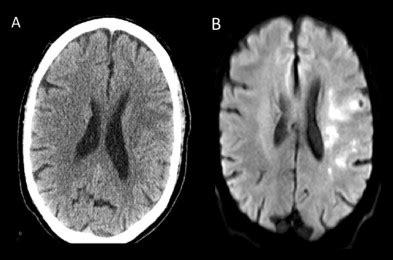

30 HQ Images Cat Scan Vs Mri For Brain / MRI scan - NHS. The scans used to be called computed axial tomography scans (cat scans). A ct scan (or cat scan) is finest matched for diagnosing bone injuries, identifying lung and chest difficulties, and sensing cancers. Pet scans provide metabolic information and are increasingly read alongside ct or mri (magnetic resonance imaging) scans, which provide anatomic information. Mri and ct scans are diagnostic imaging scans used by doctors. A ct scan (or cat scan) is best suited for viewing bone injuries, diagnosing lung and chest problems, and detecting cancers.

Ct scanners have vastly improved patient comfort because a scan can be done quickly. We explain the details and differences between ct scans and mris, and help you weigh the benefits and risks of. Mri (magnetic resonance imaging) scan is an imaging test that uses magnetic field and radio waves to detect structural abnormalities of the body whereas ct scan stands for computed tomography scan in which imaging method employs tomography. Mri provides much greater contrast between the different soft tissues of the body than computed tomography (ct) does, making it especially useful in neurological (brain), musculoskeletal, cardiovascular, and. What is the main difference between ct scan and mri and which one is best.

The scans used to be called computed axial tomography scans (cat scans). The person lies on a table that moves through a scanning ring, which looks some mri machines can be configured in ways that may reduce claustrophobia. I've also heard and read that cat scans are used more for acute injury and they don't see the soft tissues of the brain as well as an mri. Ct scans are widely used in emergency rooms because the. Computed tomography (ct), also known as computerized axial tomography (cat) scans, and magnetic resonance imaging (mri) scans are two of the most common types of diagnostic imaging. And because radiation is not used, mri scans can be conducted more frequently. mri scan vs. My docter says i need an mri but i would rather not get that. Ct scans and mri scans are two medical imaging methods that create detailed images of internal body parts, including bones, joints, and organs. Doctors typically use ct scans to identify the following. Computed tomography (ct) and magnetic resonance imaging (mri) have revolutionized the study of the brain by allowing doctors and researchers to look at the brain noninvasively. Berg keto consultant today and get the help you need on your journey. A ct scan (or cat scan) is best suited for viewing bone injuries, diagnosing lung and chest problems, and detecting cancers.an mri is suited for examining soft tissue in ligament and tendon injuries, spinal cord injuries, brain tumors, etc. Pet scans provide metabolic information and are increasingly read alongside ct or mri (magnetic resonance imaging) scans, which provide anatomic information.

You know, it's remarkable how many young people post questions here about ct and mri scans and brain tumors with never an explanation of why they're i. And because radiation is not used, mri scans can be conducted more frequently. mri scan vs. Positron emission tomography (pet) scans use a special dye that contains radioactive tracers to identify how well your organs and other tissue inside your body are functioning. Ct scans are widely used in emergency rooms because the. The person lies on a table that moves through a scanning ring, which looks some mri machines can be configured in ways that may reduce claustrophobia. Learn the similarities and differences in the two scans and how you can most often, ct scans are used to look for problems in your bones, tissues, brain or other organs. An mri is suited for examining soft tissue in ligament and tendon injuries, spinal cord injuries, brain tumors, etc. Your injuries and the urgency of your condition. These diagnostic imaging techniques have allowed for the first time the noninvasive evaluation of brain structure. The scans used to be called computed axial tomography scans (cat scans). Some people refer to a ct scan as a cat scan, which stands for computerized axial tomography. Doctors typically use ct scans to identify the following. Berg keto consultant today and get the help you need on your journey.